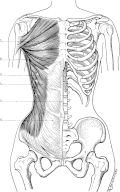

Media in category "Muscles of the human torso"

The following 90 files are in this category, out of 90 total.